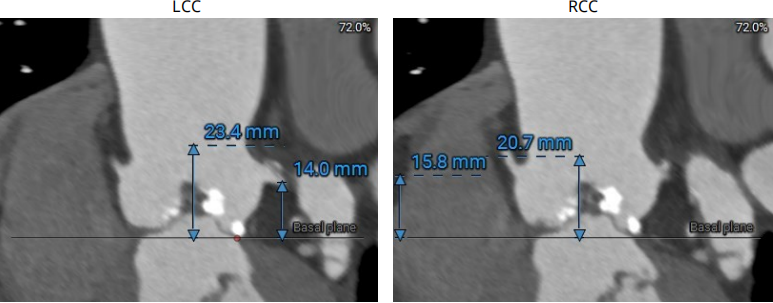

术前CT提示

主动脉瓣环折算直径22.0mm,LVOT直径20.7mm,瓣环及流出道平面可见钙化SOV 平均直径32.3mm,STJ直径30.0mm,升主动脉直径38.5mm;

左冠开口高度14.0mm;右冠开口高度15.8mm;